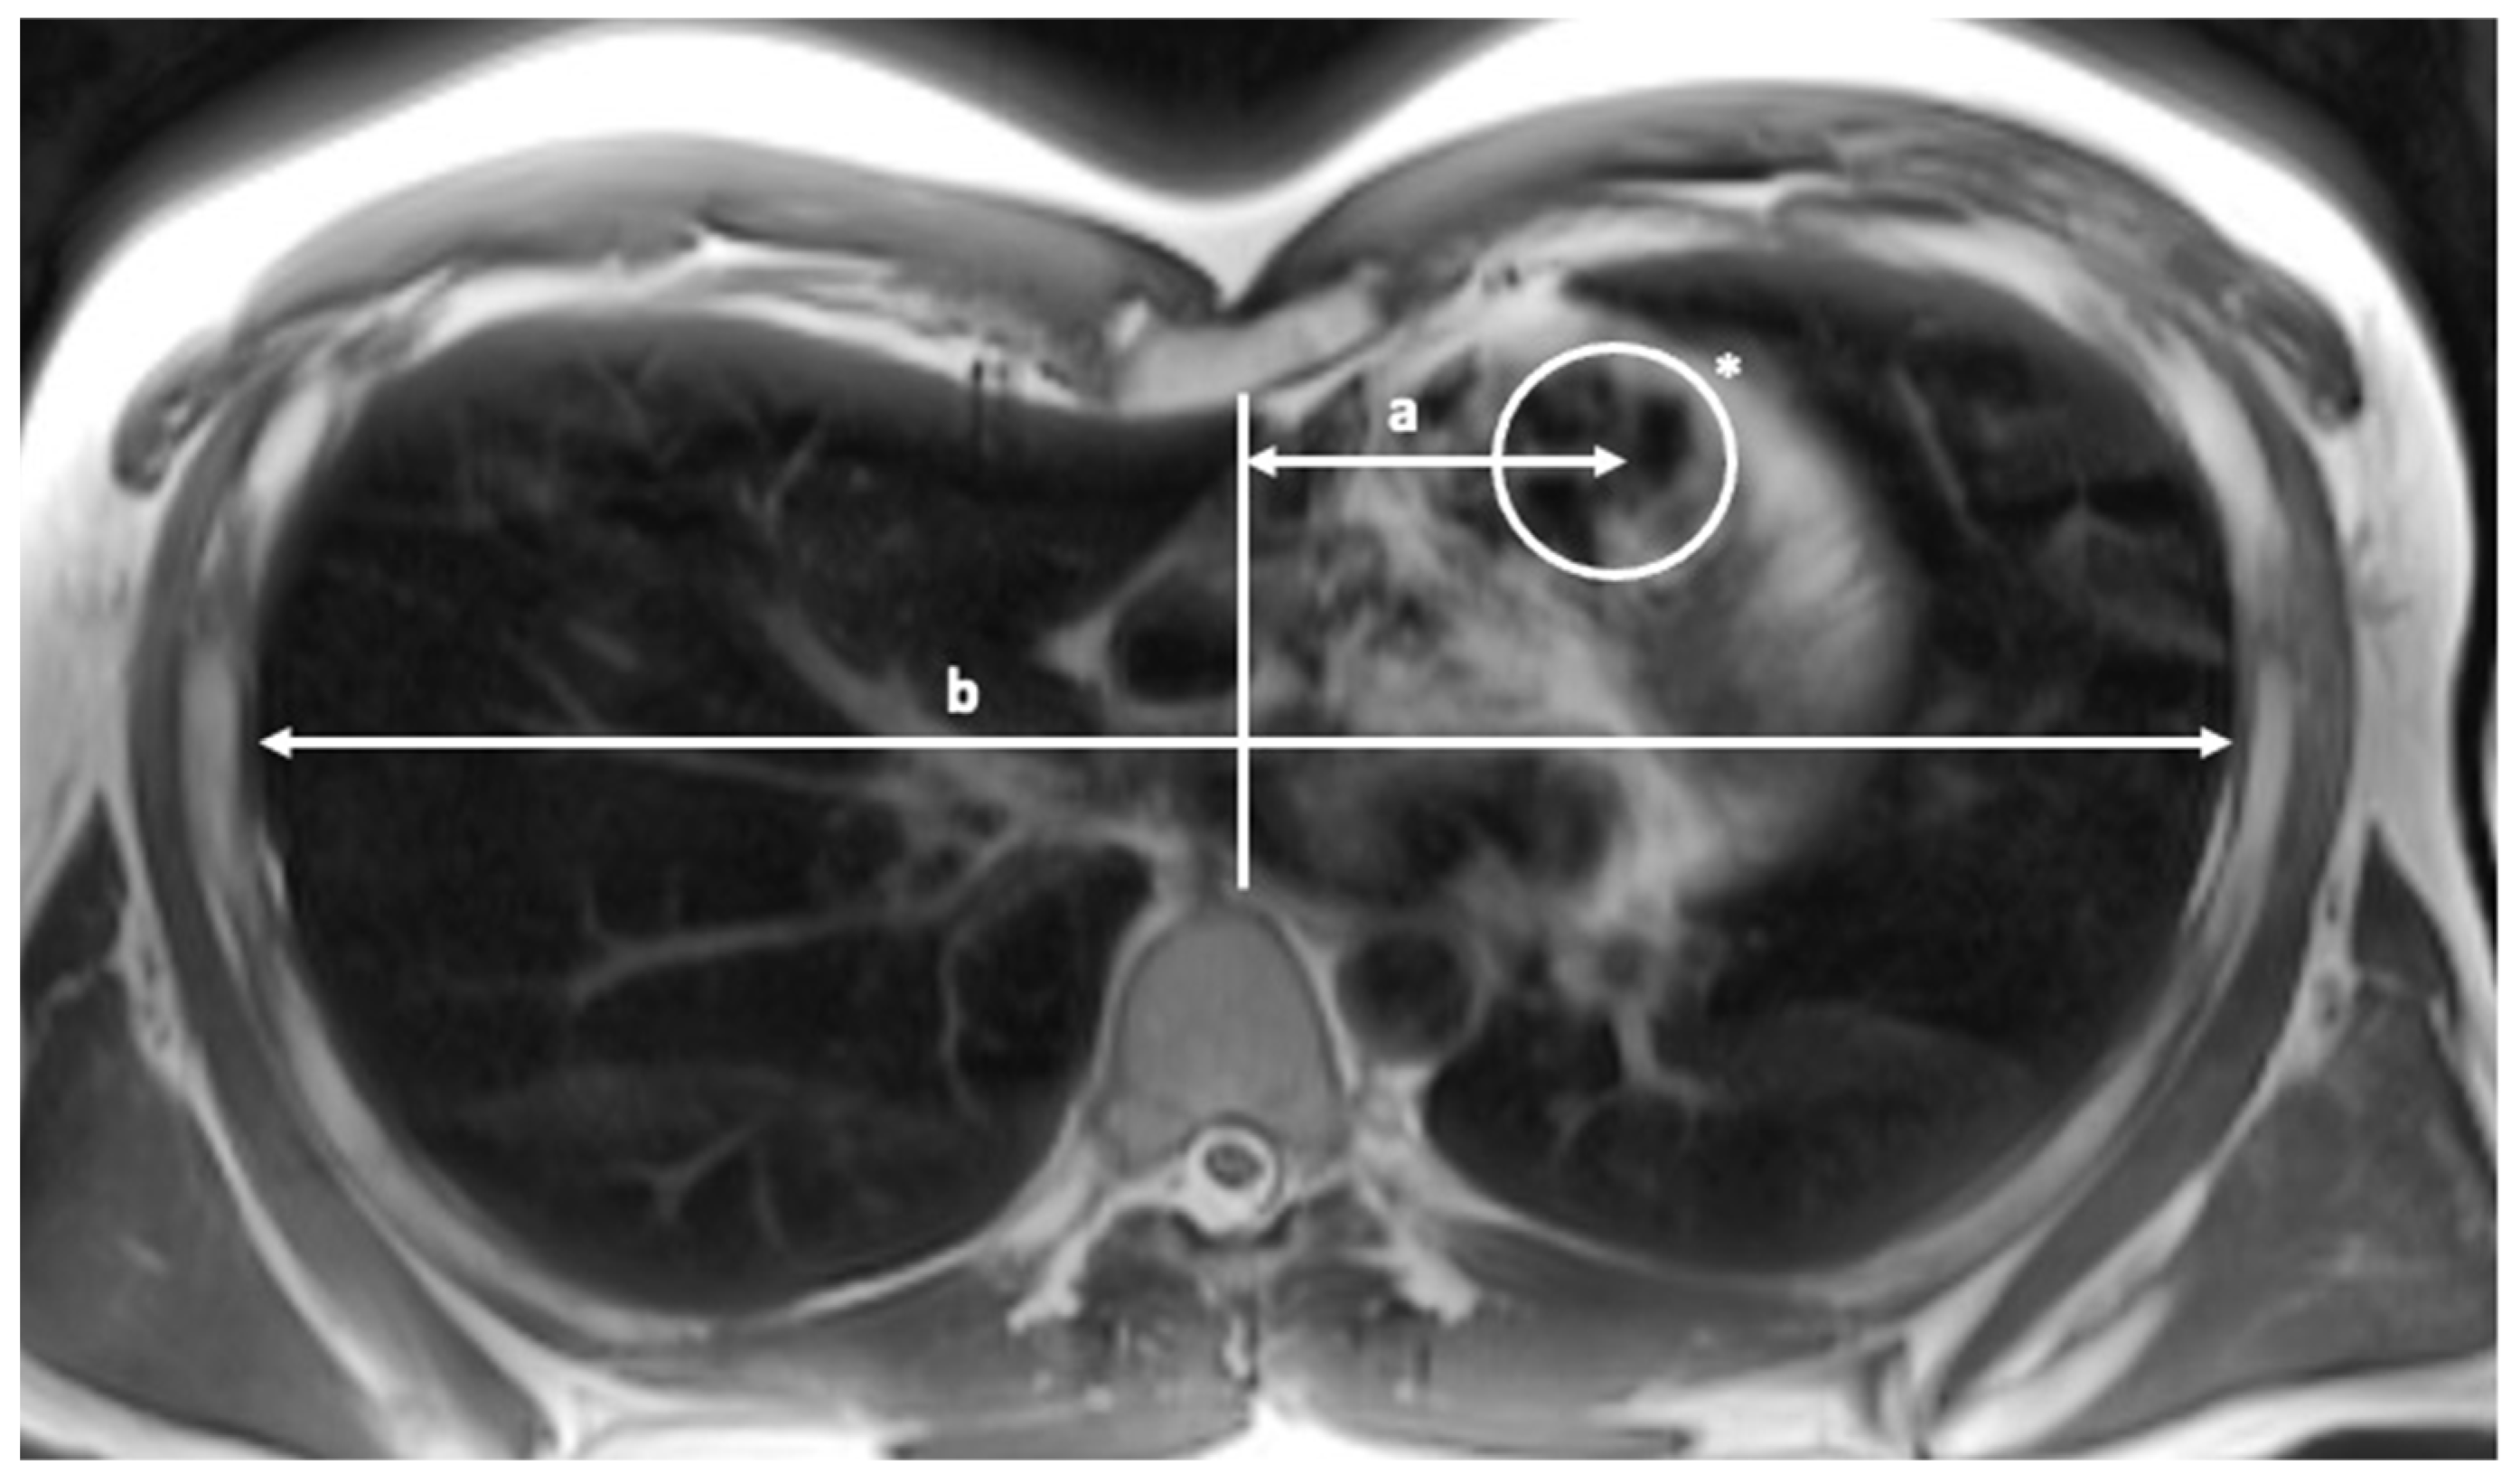

| PVRatio | Pulmonary valve position index |